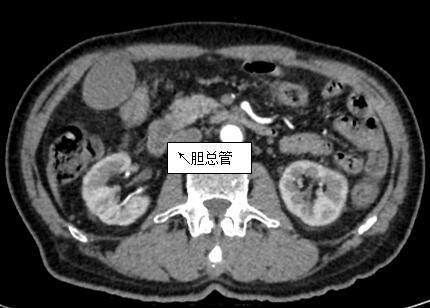

69歲王姓患者,因“發(fā)現(xiàn)無(wú)痛性黃疸1月”入院,根據(jù)患者病史,患者診斷傾向于壺腹部腫瘤所致梗阻性黃疸。予以完善腹部CT及上腹部MRI加MRCP均顯示肝內(nèi)外膽管擴(kuò)張,未發(fā)現(xiàn)明顯膽管,胰腺及十二指腸乳頭部腫瘤,且患者CA199正常。以前醫(yī)院未引進(jìn)超聲內(nèi)鏡,這類(lèi)患者到此就遇到診斷瓶頸。此患者經(jīng)過(guò)消化內(nèi)科張丹霞副主任醫(yī)師完善超聲內(nèi)鏡檢查后,可以清楚顯示膽總管下段壁內(nèi)軟組織占位。患者通過(guò)超聲內(nèi)鏡檢查診斷明確,轉(zhuǎn)至肝膽外科行手術(shù)治療。

上腹部CT圖片